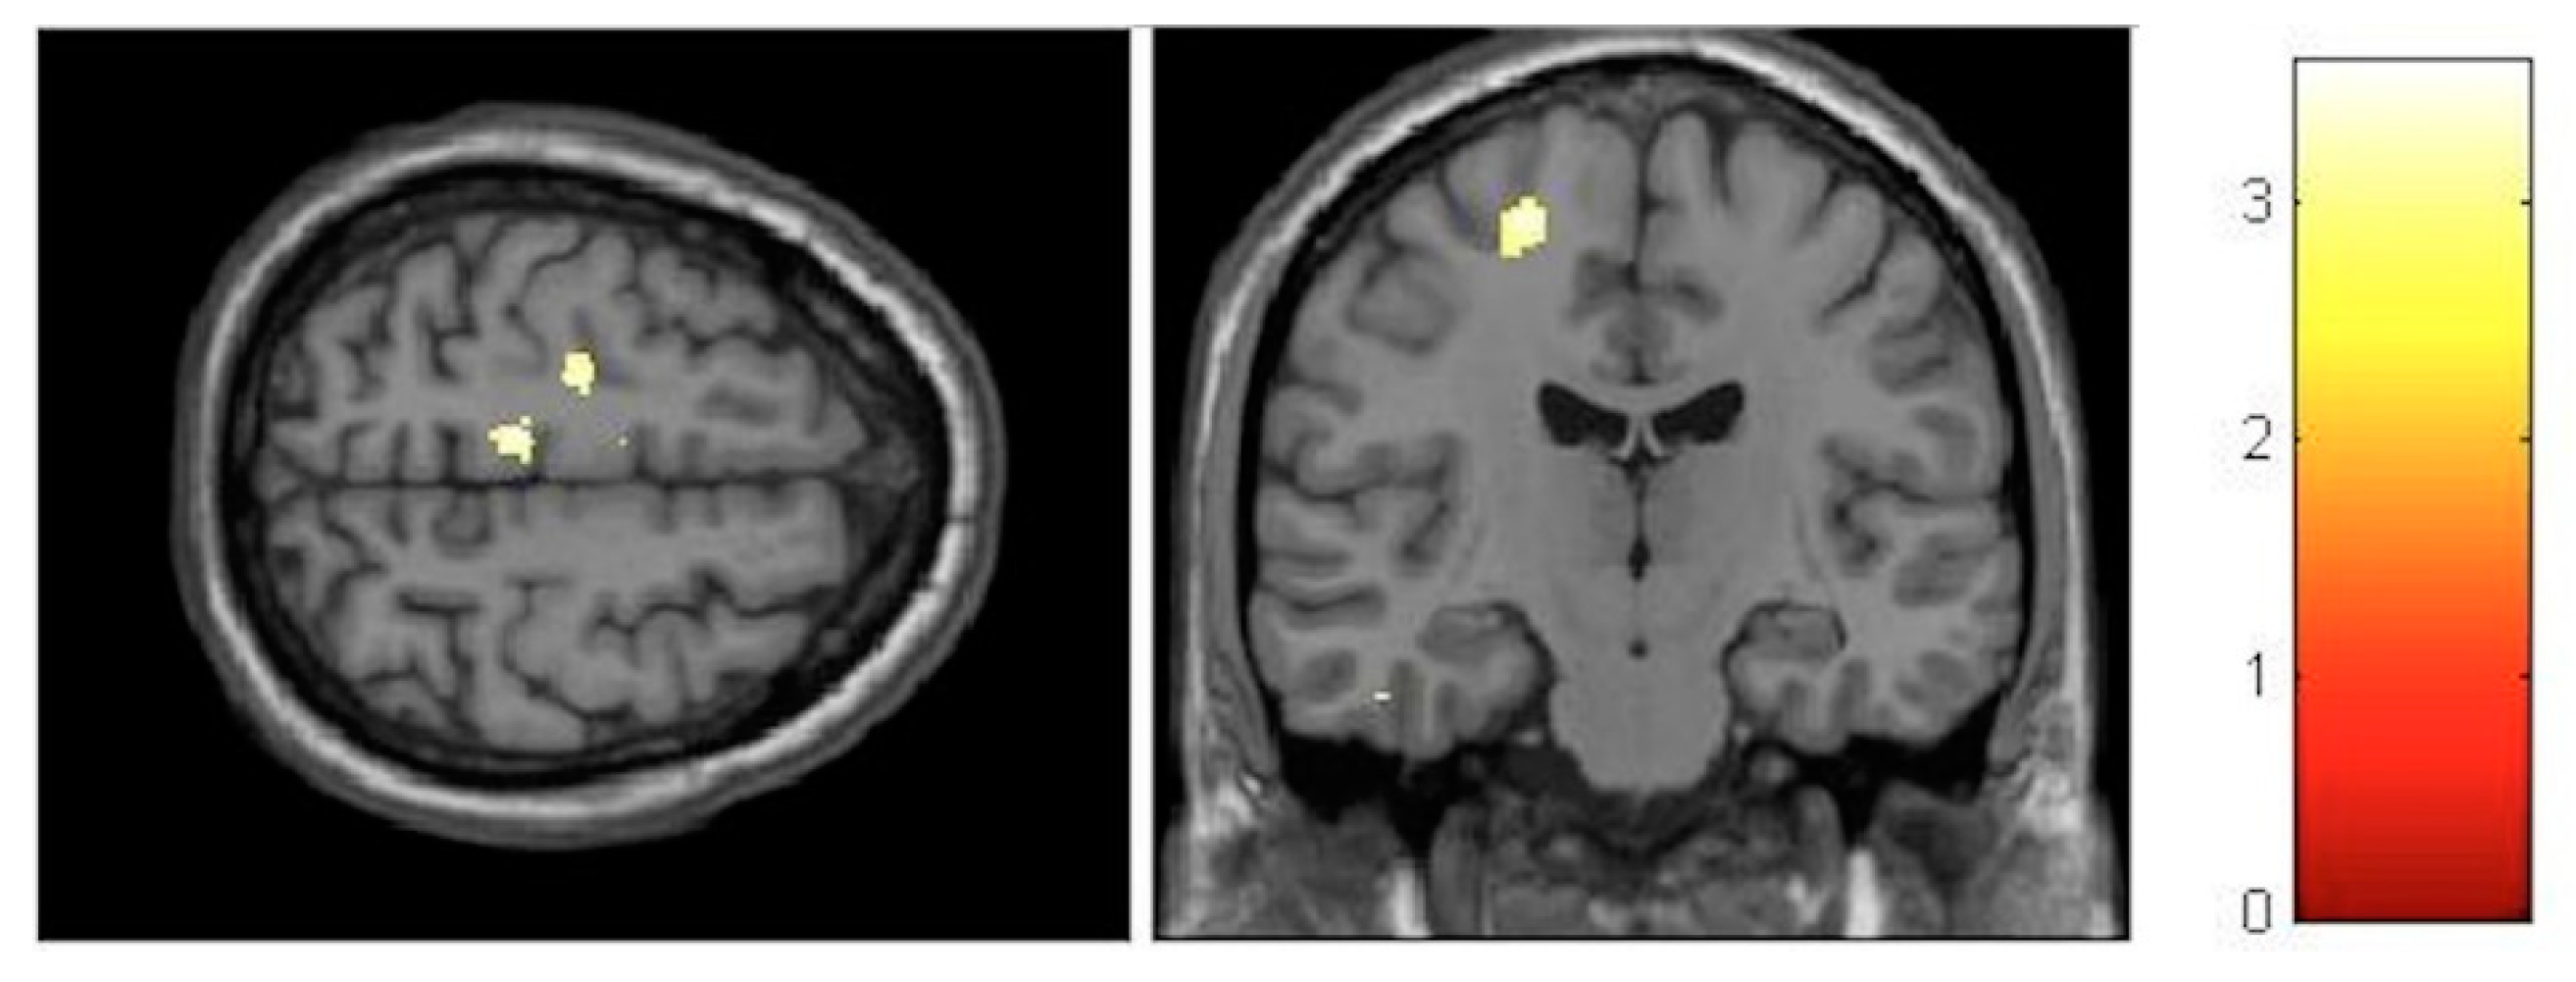

| Effect | Brain Region | Left Hemisphere MNI Coordinates (Cluster Size in Voxels) | T | d | Right Hemisphere MNI Coordinates (Cluster Size in Voxels) | T | d |

|---|---|---|---|---|---|---|---|

| Increment | Paracentral | −9, −32, 59 (1298) | 5.93 | 0.41 | 14, −36, 63 (1589) | 5.47 | 0.40 |

| Increment | Hippocampus | 34, −16, −11.5 (20) | 3.85 | 0.36 | |||

| Decrement | Insula | −32, −10, 12 (60) | 3.91 | 0.36 | 35, −20, 18 (261) | 4.36 | 0.38 |

| Decrement | Putamen | −20, 14, 0 (1879) | 5.45 | 0.40 | 24, 11, 2 (137) | 4.13 | 0.37 |

| Decrement | Cerebellum | −12, −47, −21 (511) | 5.33 | 0.40 | 11, −47, −23 (262) | 4.06 | 0.37 |